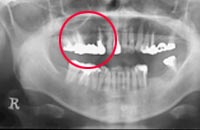

歯茎にインプラントを埋め込むのに十分な骨の厚み、幅がない場合に、当院では人工骨を移植します。

歯周組織再生療法の1つで、 歯周病等で骨が失われた部位に人工骨や自家骨(自分の骨)を移植し、骨の再生を図ります。

治療が必要な部分の歯肉を切開し、人工骨を埋め込み、再び歯肉をかぶせます。移植後、4~6カ月で骨が造成されます。

再生した骨にインプラントを埋入し、歯肉で覆います。